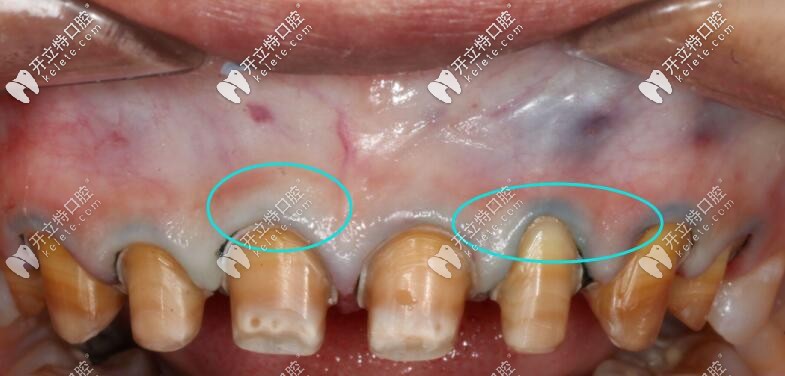

使用Procera全瓷牙修復(fù)不會出現(xiàn)以下這種情況喲↓↓↓

使用Procera全瓷牙修復(fù)不會出現(xiàn)以下這種情況